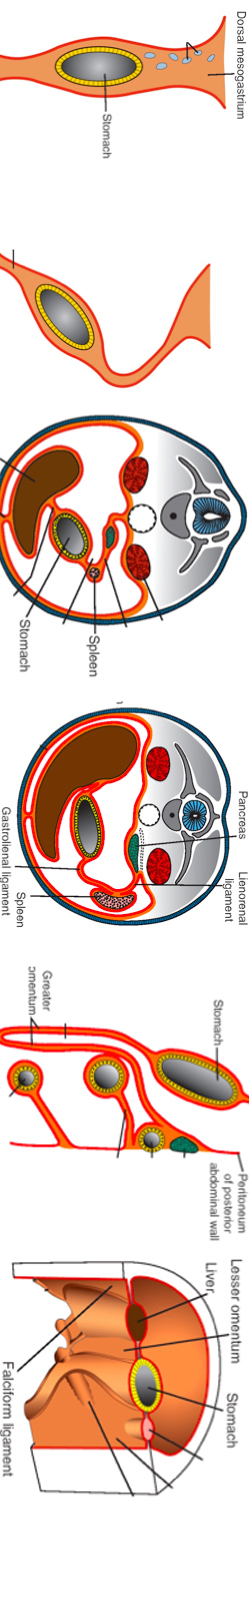

Foregut mesentery development

1) Initially, the whole gut tube and its derivatives are suspended from the dorsal body wall by dorsal mesenteries (intraperitoneal organs). The dorsal mesenteries contain vessels and nerves to and from the abdominal viscera.

2) Some organs are even connected to the ventral body wall by ventral mesenteries. These organs are the terminal part of esophagus, the stomach, and proximal portion of the duodenum. Their ventral mesenteries are derived from the septum transversum.

At first, the stomach is attached to the dorsal body wall by dorsal mesentery and to the ventral body wall by ventral mesentery.

3) As the stomach rotates, the ventral mesentery is pulled to the right and the dorsal mesentery pulled to the left.

4) At about the 5th week of development, primitive spleen starts to develop between the two leaves of dorsal mesentery. The dorsal mesentery also invests the pancreas as it develops.

5) The mesentery between the stomach and the spleen is known as gastrolienal/gastrosplenic ligament. As soon as the pancreas becomes secondarily retroperitoneal, the spleen, is connected to the body wall in close proximity to the left kidney and therefore this part of the dorsal mesentery is known as lienorenal/splenorenal ligament.

6) As a result of the rotation of the stomach about the anteroposterior axis, the dorsal mesentery of the stomach bulges down and continues to extend downwards as a four–layered greater omentum - These four layers fuse together and also fuse with the mesentery of the transverse colon hanging from the greater curvature of the stomach.

7) As soon as the liver bud grows towards the septum transversum, the ventral mesentery of the foregut further develops into the lesser omentum and the falciform ligament. The falciform ligament extend from the liver to the ventral body wall and the lesser omentum extend from the stomach and upper duodenum to the liver.

8) Interestingly, the posterior leaf of the dorsal mesenteries and the peritoneum of the posterior body wall degenerate for some organs (which originate from the gut tube) rendering them retroperitoneal. These organs are known as secondarily retroperitoneal (because they are first intraperitoneal then eventually become retroperitoneal). These organs include the pancreas, the duodenum (except the proximal portion), ascending colon, descending colon, and sigmoid colon.